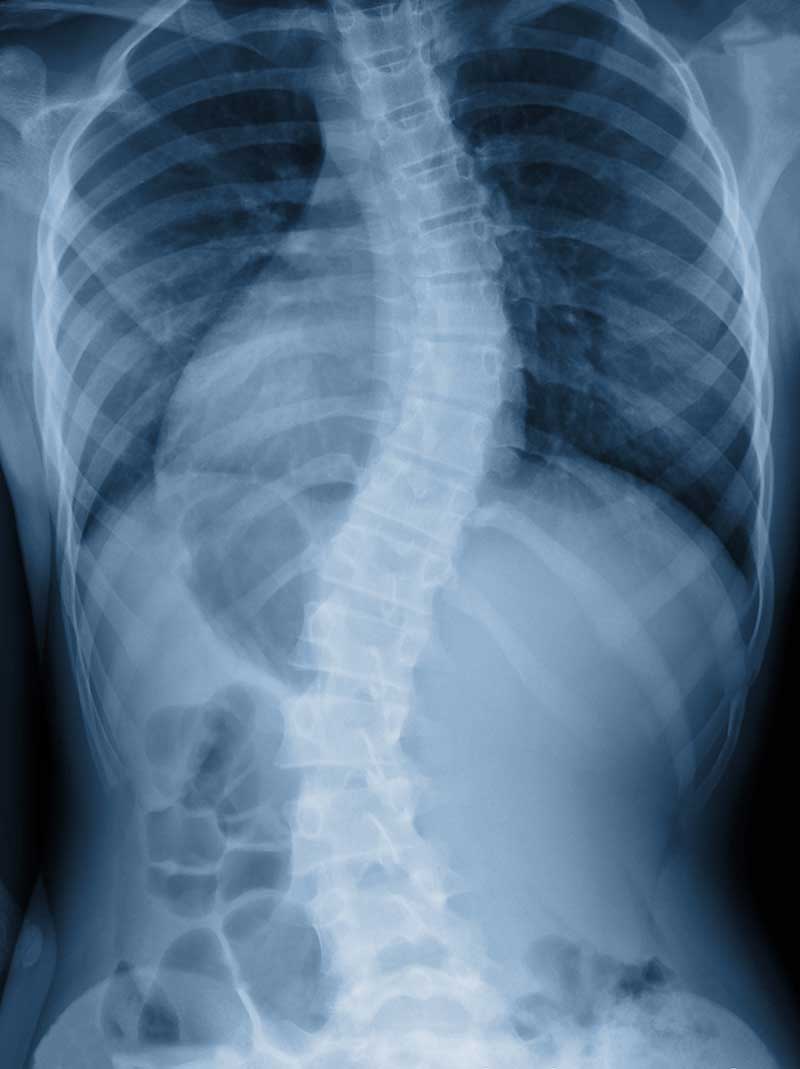

If you have scoliosis, your spine curves to the left and/or right. The spine should curve in and out along its vertical path but shouldn’t deviate sideways as it does with scoliosis.

Nonstructural scoliosis is typically caused by muscle spasms, inflammation, or having different leg lengths. Treating the underlying cause corrects nonstructural scoliosis. Structural scoliosis is a permanent spinal curvature.